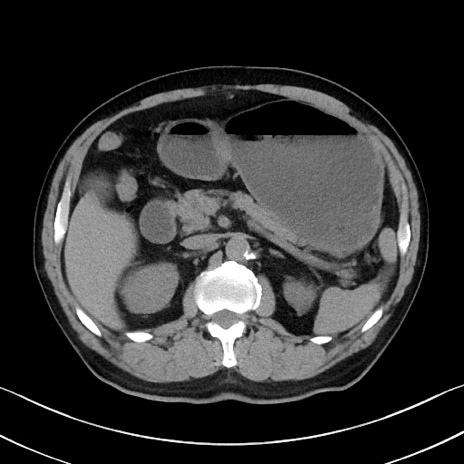

症例35(横断像)

冠状断像

【症例】70歳代 男性

【主訴】腹部膨満、嘔吐

【現病歴】昨日より腹部膨満感出現。本日増悪し、仙痛出現。嘔吐あり、受診。

【既往歴】糖尿病、胆摘後

【身体所見】BP 149/80mmHg、HR 74/min、BT 35.9℃、腹部:膨満、軟、圧痛なし。腸雑音減弱あり。上腹部正中切開瘢痕あり。

【データ】WBC 13500、CRP 1.72